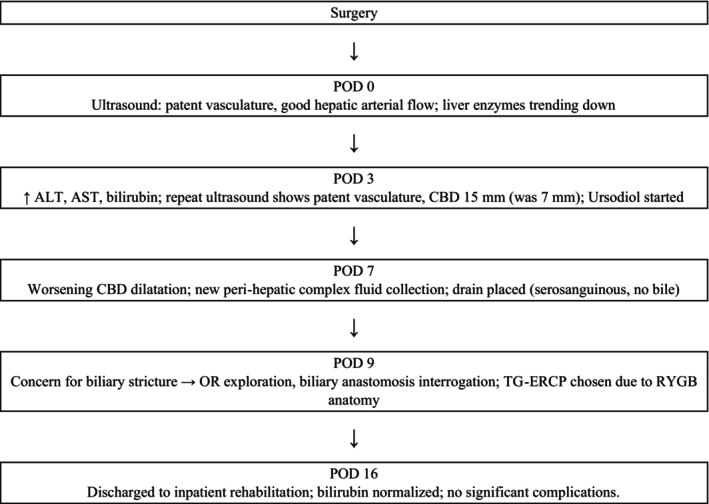

Biliary complications after orthotopic liver transplantation (OLTx) have a high incidence with inherent risks. Given the rise of obesity and subsequent bariatric surgery, there are new challenges for management, particularly in the setting of bypass anatomy, which is not well described. Trans‐gastric remnant endoscopic retrograde cholangiopancreatography (TG‐ERCP) is a novel technique that could evolve into a primary tool for the diagnosis and treatment of biliary complications after OLTx. A 35‐year‐old female with a history of Roux‐en‐Y gastric bypass (RYGB), decompensated alcoholic cirrhosis, and a MELD of 40 underwent standard OLTx. The postoperative course was complicated by rising liver function tests and common bile duct (CBD) dilatation without graft biliary tree dilation. Due to her bypass anatomy, TG‐ERCP was used to diagnose a biliary stricture which was treated with CBD stenting. A gastric remnant gastrostomy tube (G‐tube) was placed as easy access for all interval ERCP interventions until stricture resolution. As metabolic dysfunction‐associated steatotic liver disease becomes a larger transplant indication, centers will undoubtedly encounter more recipients with RYGB anatomy. When compared to alternative options, TG‐ERCP should be the primary tool for the diagnosis and treatment of postoperative biliary complications, given its high success rate with fewer complications and graft vascular injuries. Future cohort‐based studies are necessary to validate this approach and the proposed treatment algorithm.

Immediately after surgery, ultrasound demonstrated patent vasculature with good hepatic arterial flow (Figure 1). The patient’s liver enzymes initially began to downtrend until postoperative day (POD) three when there was an elevation in alanine transaminase (ALT), aspartate aminotransferase (AST), and bilirubin (from 28.9 mg/dL preoperatively to 23.5 mg/dL on POD2 to 29.7 mg/dL on POD3). Repeat ultrasound was reassuring with patent vasculature; however, a distended common bile duct (CBD) to 15 mm was visualized (from 7 mm). The patient was started on ursodiol; however, her bilirubin remained elevated over the next 6 days. Ultrasound on POD7 revealed worsening CBD dilatation with a new peri‐hepatic complex fluid collection. The fluid collection lay behind the right lobe and extended into the pericolic gutter, measuring 11.7 × 8.0 × 7.0 cm. An ultrasound‐guided drain was placed with return of serosanguinous fluid and no evidence of bile; thus, postoperative biloma was effectively ruled out.

Postoperatively, the patient’s bilirubin and liver enzymes began to decline. She had no other significant postoperative complications. After 7 days in the hospital, she was discharged to inpatient rehabilitation with normalizing bilirubin. She was scheduled to undergo a repeat TG‐ERCP for stent removal, this time in the endoscopy suite, given the gastric remnant access via the G‐tube negates the need for a repeat operative exposure.